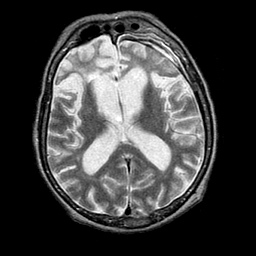

La maladie de Pick est une démence associée à la détérioration des lobes frontaux et temporaux du cerveau. C'est une protéinopathie de la famille des dégénérescences lobaires frontotemporales.

En 1892, le neurologue et psychiatre tchèque Arnold Pick a été le premier à décrire le syndrome clinique et les inclusions neuronales caractéristiques, les corps de Pick, associés à cette maladie. Aujourd'hui le terme de maladie de Pick est de moins en moins utilisé et la maladie en question correspond à ce que l'on nomme à ce jour variante frontale de la dégénérescence lobaire frontotemporale (DLFT). La maladie de Pick est caractérisée par une forme et une localisation tout à fait particulière des agrégats de protéines tau (corps de Pick), retrouvé à l'examen anatomopathologique du cerveau (ce qui nécessite une autopsie).